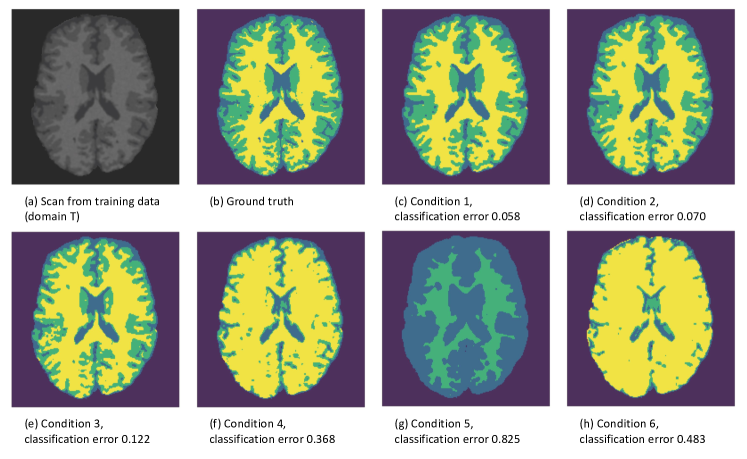

Figure 1: Examples of segmentations with corresponding acquisition parameter settings. In the controlled experiment, we compared scanner 1 (domain T: training data) with the other 6 scanners (domain U: unseen data). The difference between scanner 1 and the additional 6 scanners ranged from subtle to severe differences in acquisition parameters. The arrow gives an indication of the ordering of the data sets based on similarity, as compared to scanner 1.

Based on brain tissue segmentations of real human brain data, we obtained a number of different MRI data sets, ranging from subtle to severe differences in protocol (acquisition parameters). Figure 1 shows examples of segmentations with corresponding acquisition parameter settings. More information regarding the data and parameter settings can be found in Section 3.1.

In each condition of the controlled experiment, the two domains were specified. Specifically, scanner 1 (domain T: training data) was compared with the other 6 scanners (domain U: unseen data). In condition 1, we compared scanner 1 with scanner 2, with only a very small difference in acquisition parameters (i.e. small difference in TR). In the following three conditions, scanner 1 was compared with scanners 3, 4 and 5, respectively. The difference in acquisition parameters increased with each condition, by an increase in the value for TR. In condition 5, we compared scanner 1 with scanner 6, both 3.0 Tesla scanners but with very different acquisitions parameters. Lastly, condition 6 compared scanners 1 and 7. Here we compared scanners with different magnetic field strengths: a 3.0 Tesla scanner with a 1.5 Tesla scanner.

Figure 3: Images based on predicted tissue classes for all six conditions, where the algorithm was built on training data (patches from 15 scans) and applied to unseen data (1 scan). The classification errors are denoted below the images.

Figure 3 illustrates the effect of data set similarity on the performance of a tissue classifier (built on training data) when applied to a different data set (unseen data), ranging from subtle to severe differences in acquisition parameters between data sets. Results showed that as the difference between the data sets increased, the tissue classification performance decreased dramatically (e.g. conditions 4-6). This is also illustrated in Figure 4, in which the black dots show the tissue classification performance as presented in Figure 3. Figure 4 further illustrates that as the data similarity grew, the informativeness of the training data set increased.